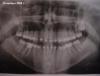

Премоляр Опубликовано 16 мая, 2010 Поделиться Опубликовано 16 мая, 2010 Мало данных...не вижу изначальной ситуации.По тому что есть:1-центр.в.ч. смещен вправо.Вероятно связано с микродентией 12 и ретенцией 132-сагит.щель увеличена,перекрытие "углублено". Это связано с удалением 4рок и естеств.изменением наклона резцов при попытке закрытия промежутков. В данном случае целесообразно раскрытие места под импланты в обл.удаленных 4рок,т.к. закрытие места приведет к усугублению "несоответствия соотн.челюстей"(и дальнейшим проблемам...) А вообще-случай требует тщательной диагностики.Мои теории-это всего лишь предположения...и никак не руководство к действию. Ссылка на комментарий

Force Опубликовано 20 мая, 2010 Поделиться Опубликовано 20 мая, 2010 По личной просьбе пац-ки скажу свое мнение. Перелечивание - самое ужасное в ортодонтии. Просто ужасно. Поэтому прокомментировать этот случай могу лишь "со своей колокольни" ибо расхлебывать это кому-то все таки придется.Комментарии будут содержать некоторые термины, чтобы вы могли это мнение показать вашему ортодонту. может, ему что и пригодится.Итак 1. Необходима коррекция центр линии на в.ч. после определения центрального соотношения, возможно она будет не так выражена или вообще не выражена2. Установка 13 зуба в зубную дугу3. Ввиду особенностей наклона окклюзионной плоскости и небольшой сагитальной щели я бы не стал раздвигать под винты (угол еще больше увеличится), а поставил бы аппарат типа джаспера для зубоальвеолярной коррекции.Другой вариант - короткая тяга по 2 классу с интрузией н.чел. резцовЕще один вариант - реконструкция окклюзионной плоскости на MEAW, но вряд ли кто из докторов вам в этом поможет, если вы не в москвеВот как то так. Ссылка на комментарий